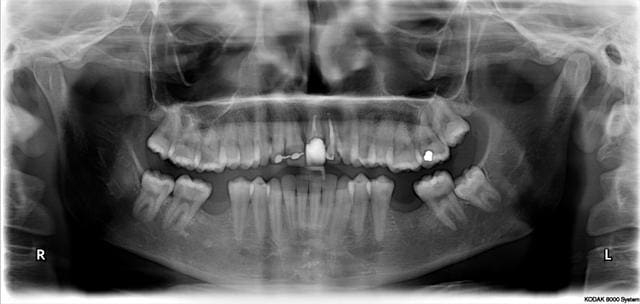

Au fauteuil, cata, elle a vu un dentiste qui lui a soigné toutes les dents du fond il y a un an et demi (cf pano...) mais apparemment pas les caries.

les radios

Pano ziyd19 - Eugenol

R21 q4vskw - Eugenol